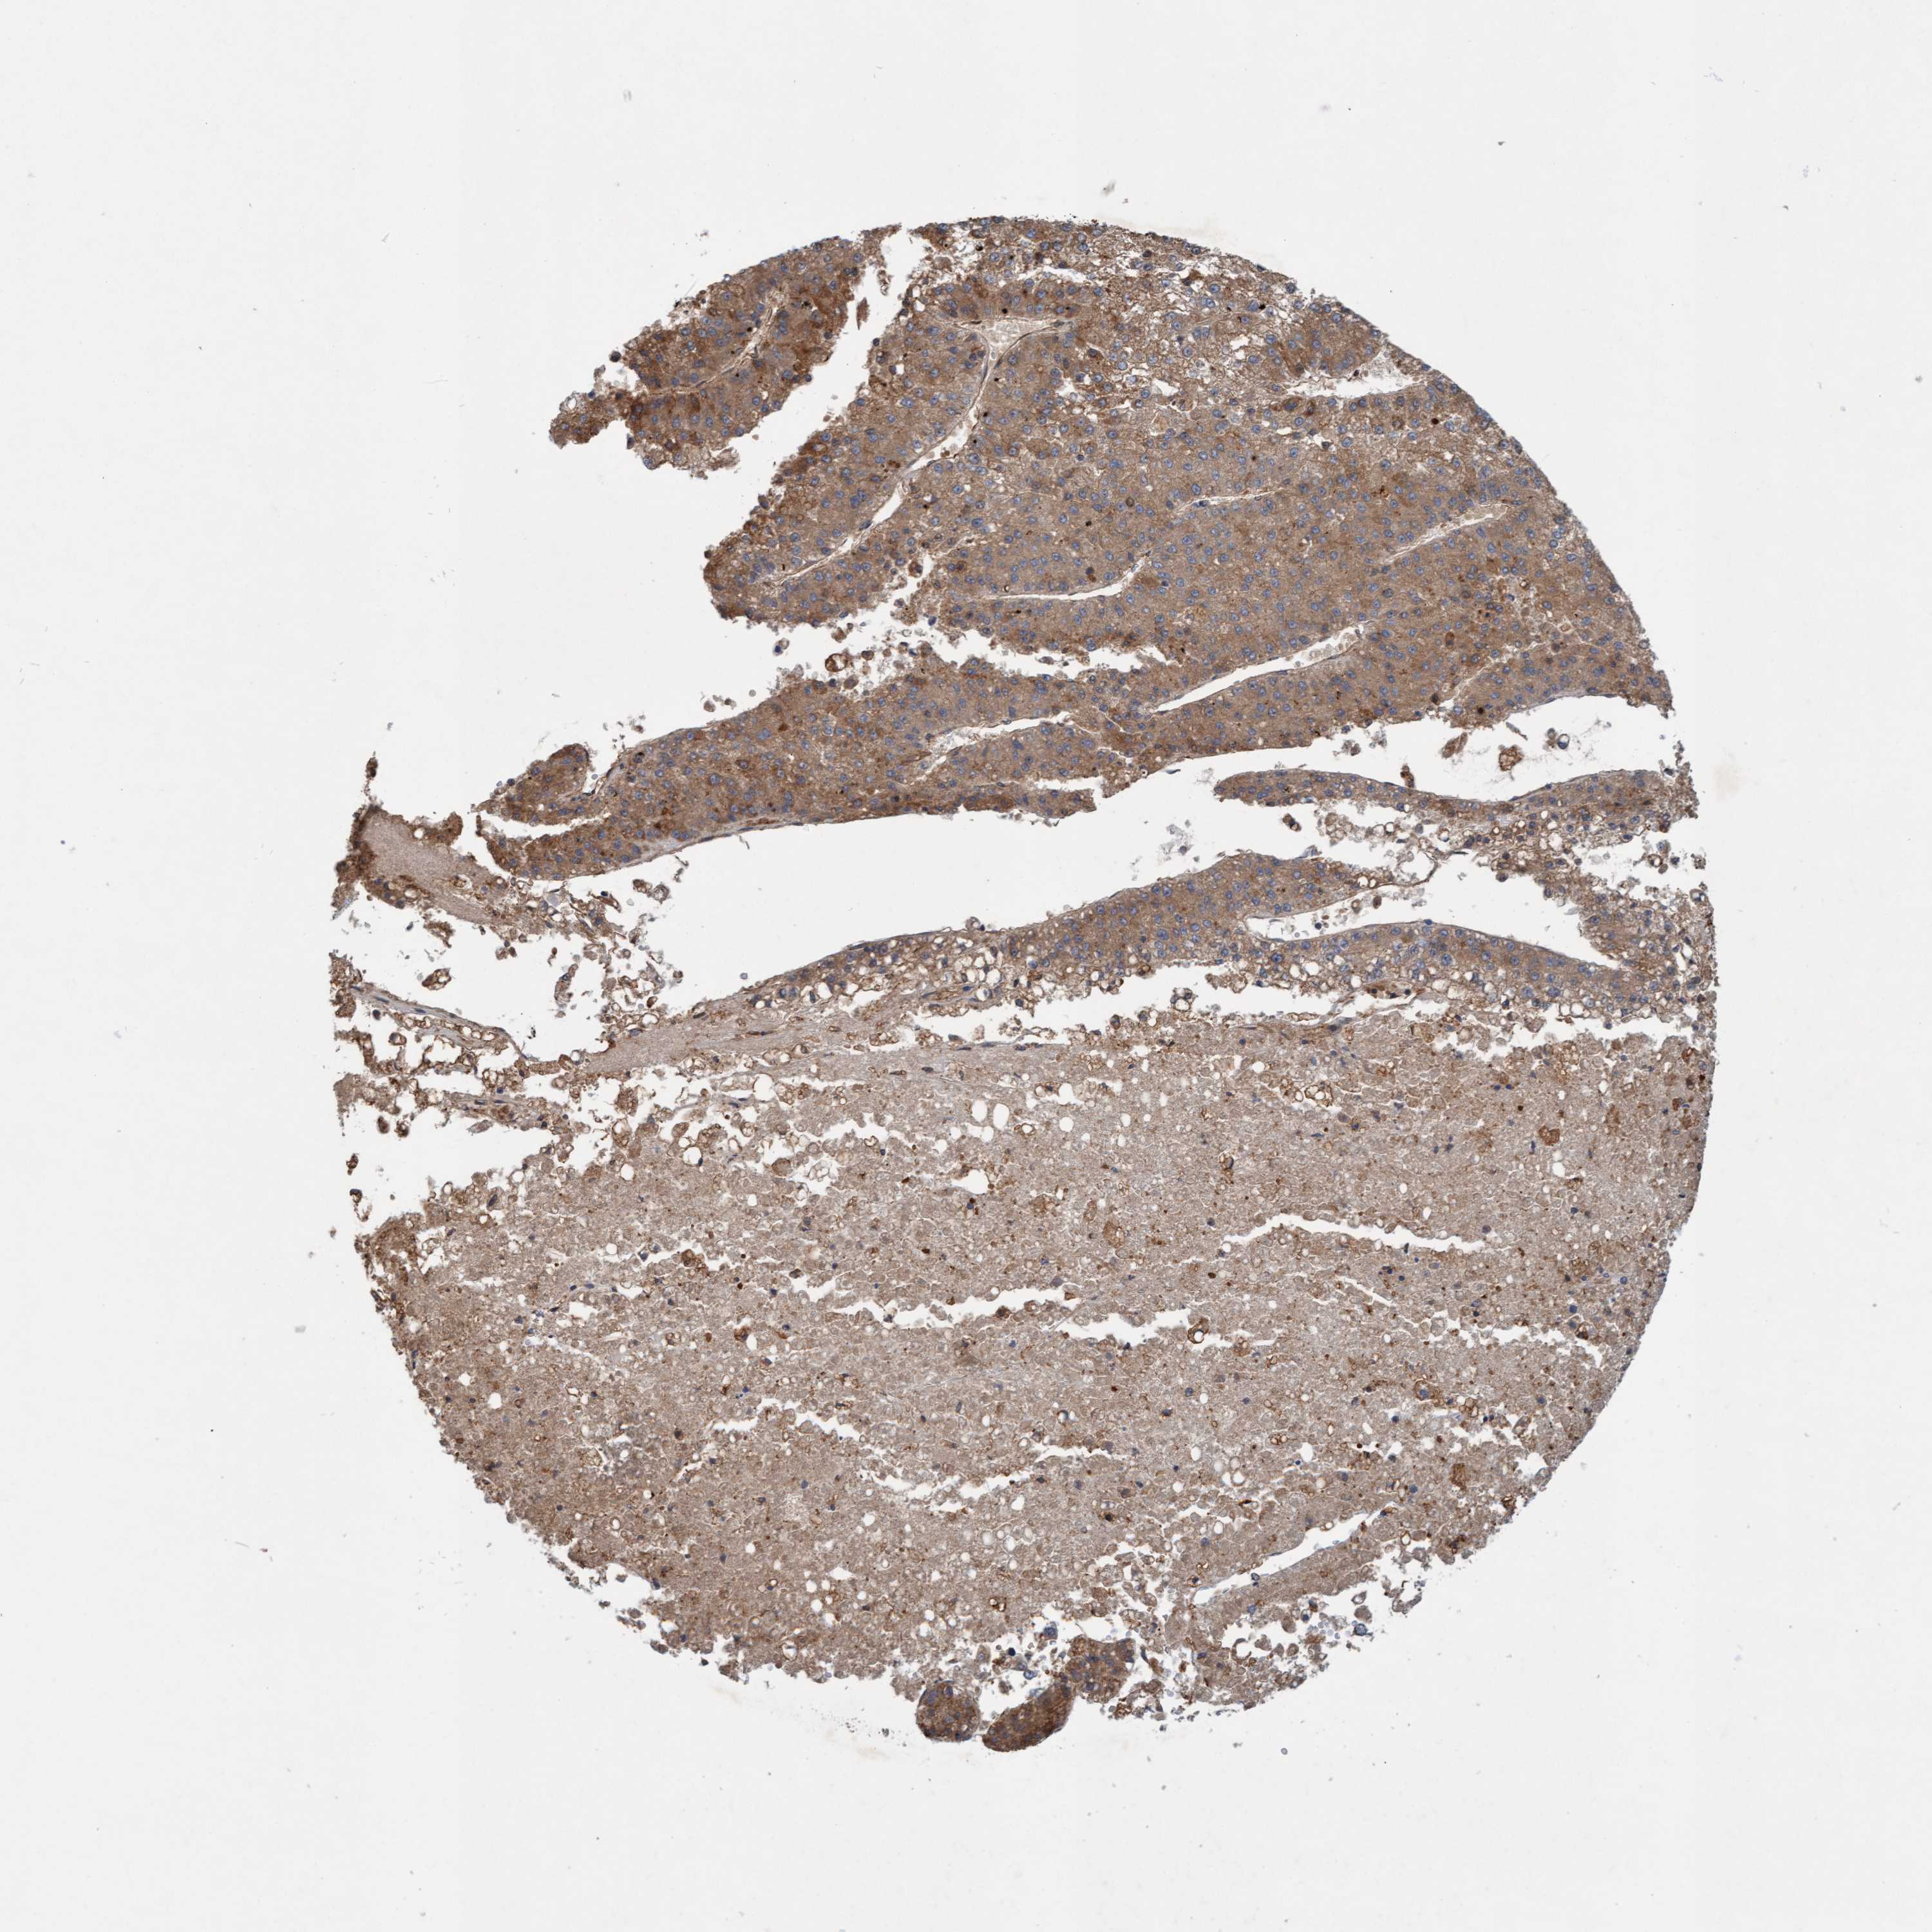

LIVER CANCER - Protein expressioni

A mouse-over function shows sample information and annotation data. Click on an image to view it in a full screen mode. Samples can be filtered based on level of antibody staining by selecting one or several of the following categories: high, medium, low and not detected. The assay and annotation is described here.

Note that samples used for immunohistochemistry by the Human Protein Atlas do not correspond to samples in the TCGA dataset.

Antibody stainingi

Antibody staining in the annotated cell types in the current human tissue is reported as not detected, low, medium, or high, based on conventional immunohistochemistry profiling in selected tissues. This score is based on the combination of the staining intensity and fraction of stained cells.

Each image is clickable and will lead to virtual microscopy that enables deeper exploration of all samples and also displays staining intensity scores, fraction scores and subcellular localization as well as patient and tissue information for each sample.

Antibody HPA021425

Antibody HPA024423

Staining

High

Medium

Low

Not detected

Intensity

Strong

Moderate

Weak

Negative

Quantity

>75%

75%-25%

<25%

None

Location

Nuclear

Cytoplasmic/membranous

Cytoplasmic/membranous,nuclear

Cholangiocarcinoma

Carcinoma, Hepatocellular, NOS